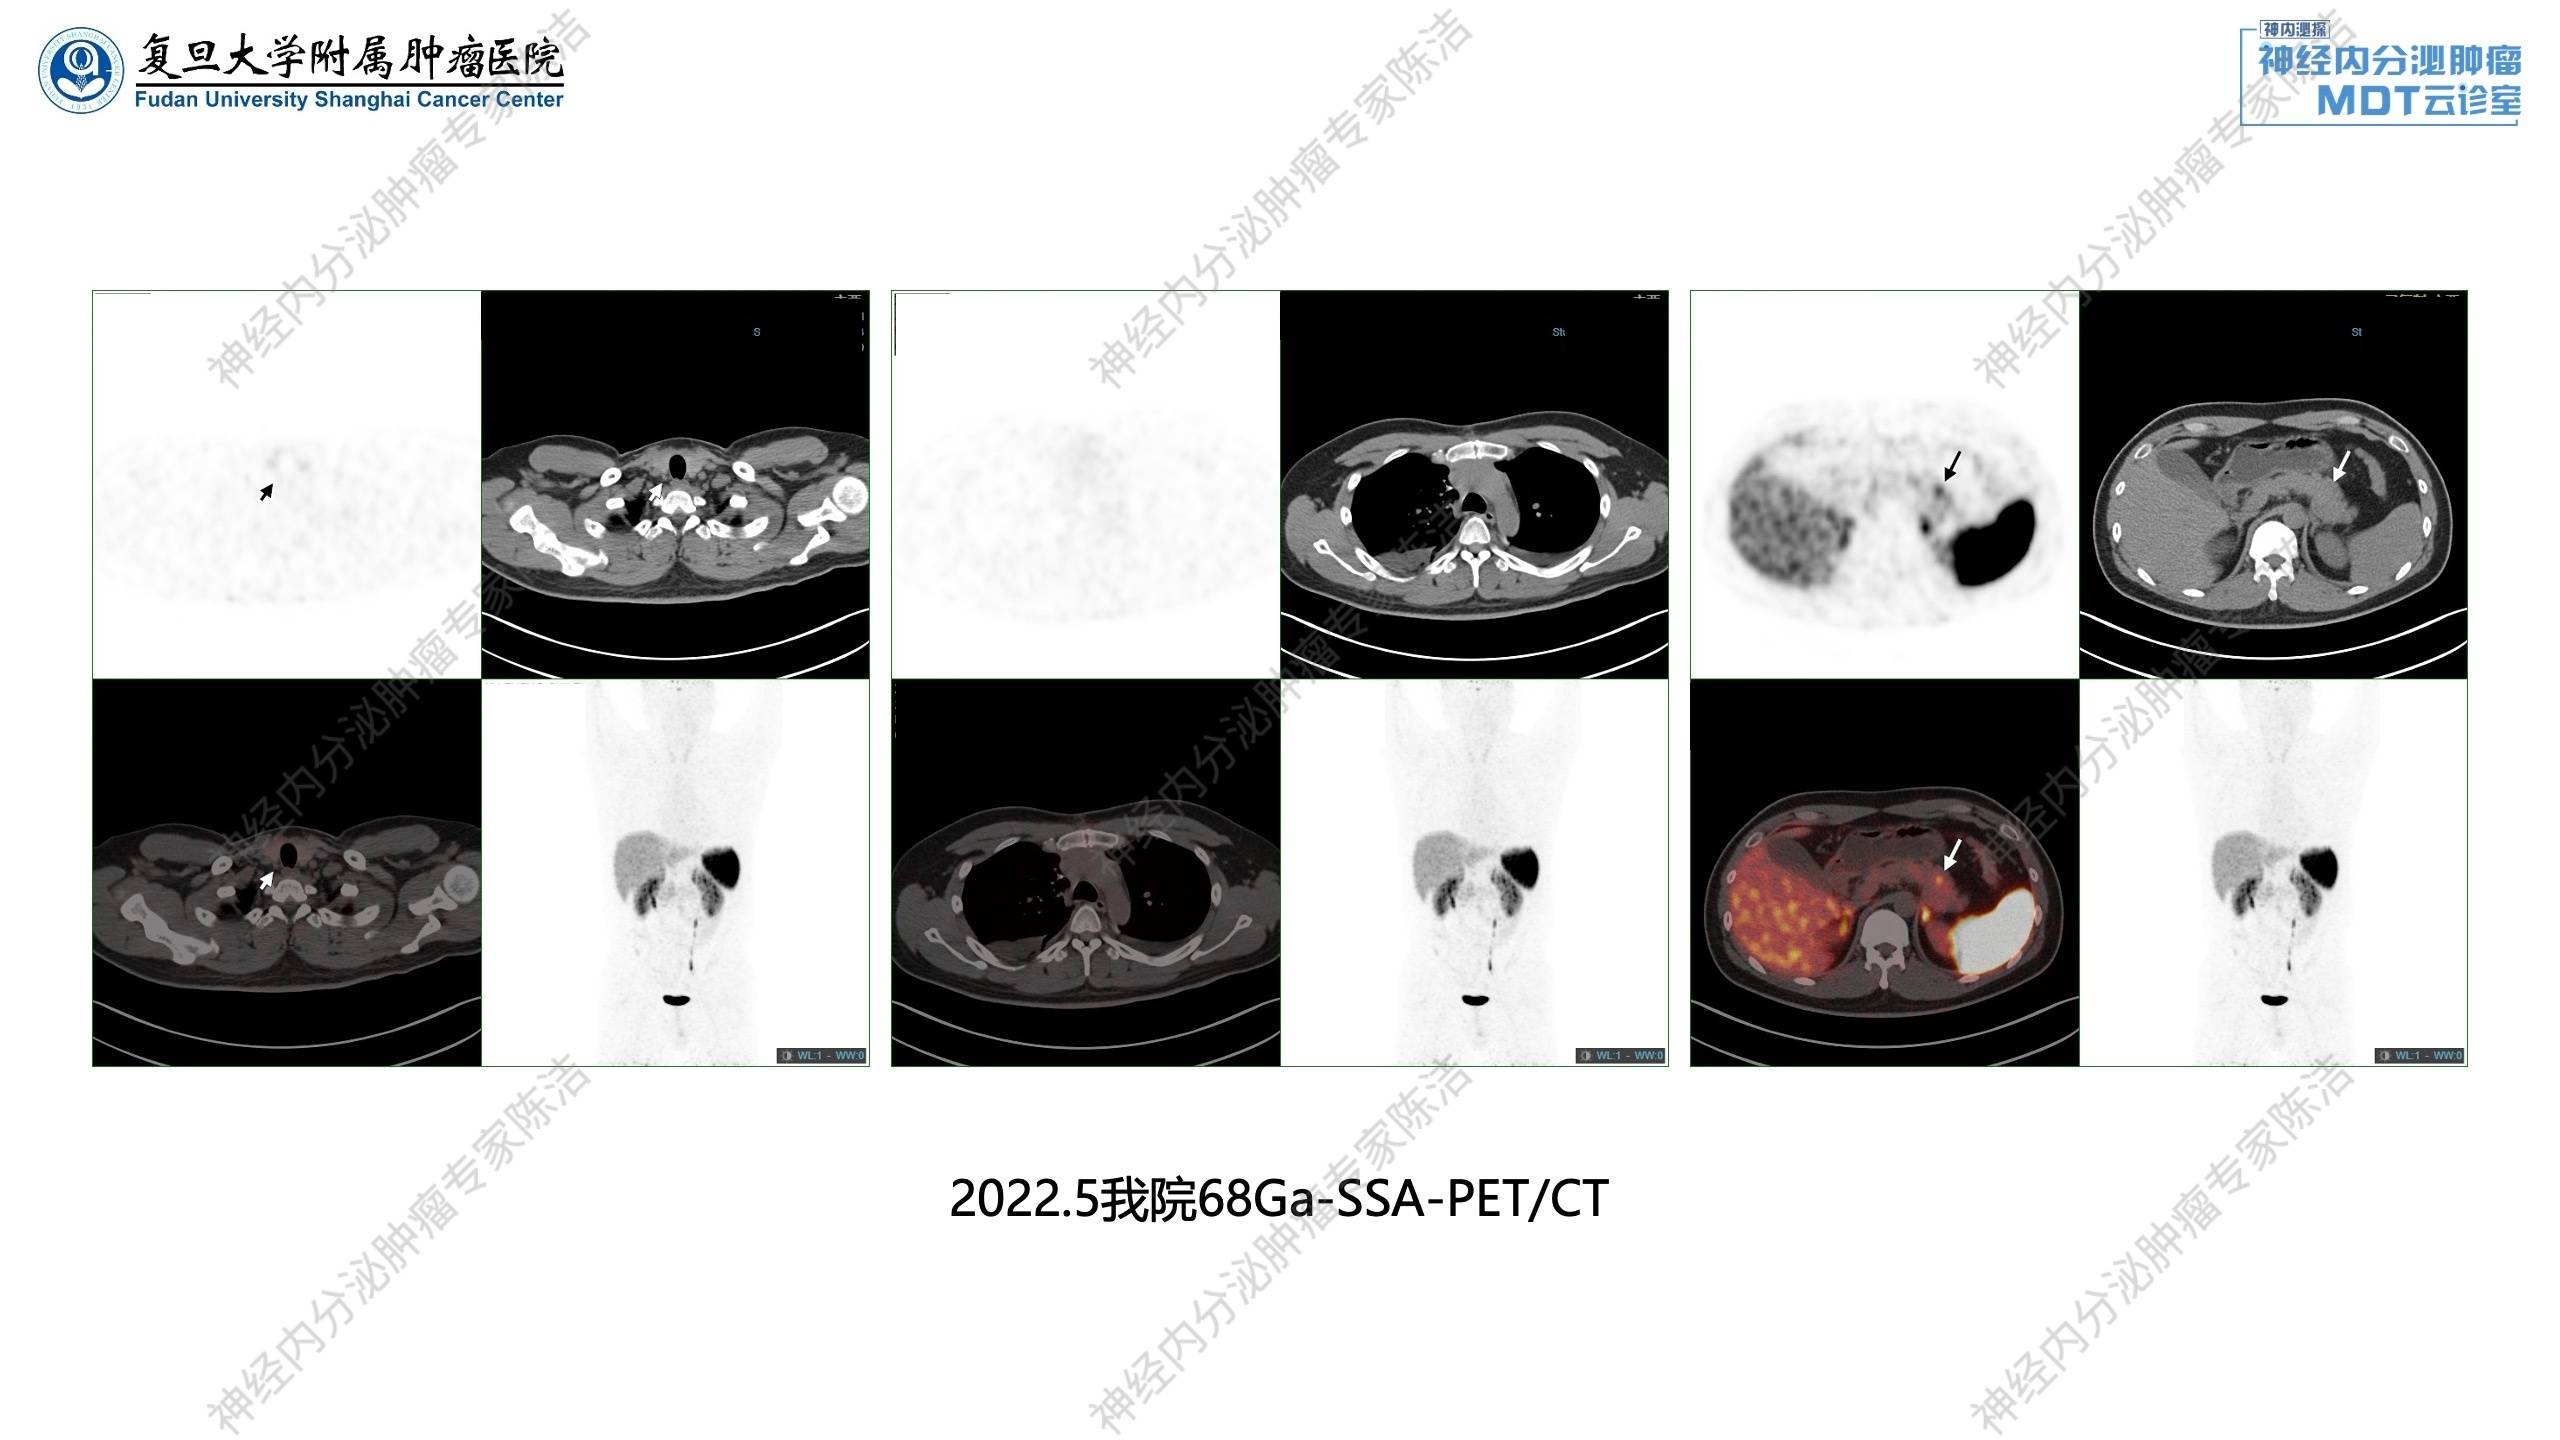

2022年5月:68Ga-SSA-PET/CT提示胸腺不典型类癌术后,局部未见NOC摄取异常增高灶;胰腺体尾部小灶性NOC摄取增高。甲状腺右叶后方结节影,未见NOC摄取增高。

幻灯片37.jpg

核医学科徐俊彦教授:该患者术前18F-FDG-PET/CT显示前上纵隔分叶状肿块,FDG代谢轻度增高。术后68Ga-SSA-PET/CT扫描,提示纵隔肿瘤已切除,但在胰体尾发现了小灶性的SSTR高表达病灶,提示胰腺神经内分泌瘤。甲状腺右叶后方存在微小软组织结节(<5mm),MIBI显像没有明显浓聚。这可能是因为病灶太小,且患者PTH和血钙仅轻度升高,功能不活跃,导致MIBI灵敏度不高。